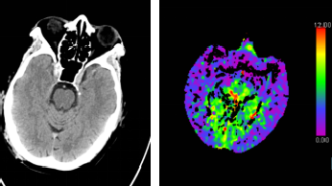

腦CT沒事就代表大腦沒事嗎?深入探討腦部健康與CT檢查的關系,腦部健康與CT檢查,CT無異常是否代表大腦無隱患?

摘要:腦部健康與CT檢查的關系并非簡單等同。雖然腦CT檢查可以檢測腦部結構異常和損傷,但并不能完全排除所有潛在疾病。腦部健康涉及更多方面,如功能狀態、神經傳導等,CT檢查無法全面評估。腦CT沒事不代表大腦一定沒問題,...